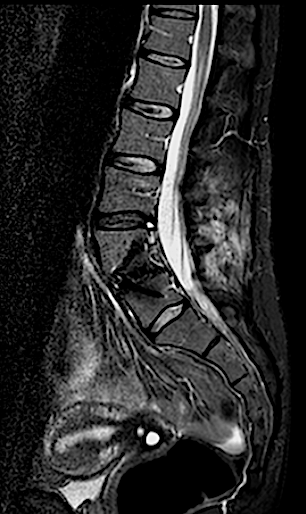

Paciente de 34 años con lumbalgia mecánica refractaria de años de evolución con progresión de la clínica.

En la RM lumbar de control se apreciaba edema en L5-L6 que se interpretó como secundario a sobrecarga mecánica a dicho nivel. Se decidió una fijación percutánea (MIS) L5-L6.

Tras la fijación percutánea, la paciente seguía presentando lumbalgia mecánica (de menor intensidad). Tras agotar opciones de tratamiento conservador, atribuimos como causa la discopatía incipiente L4-L5 (que había progresado).

Se intervino mediante un abordaje abierto (me parece muy a tener en cuenta que, las reintervenciones de los niveles adyacentes en cirugías percutáneas (MIS) deben realizarse en abierto para conectar el sistema!!) sin complicaciones, con buen resultado radiológico y clínico inicial. La paciente fue remitida a Rehabilitación.